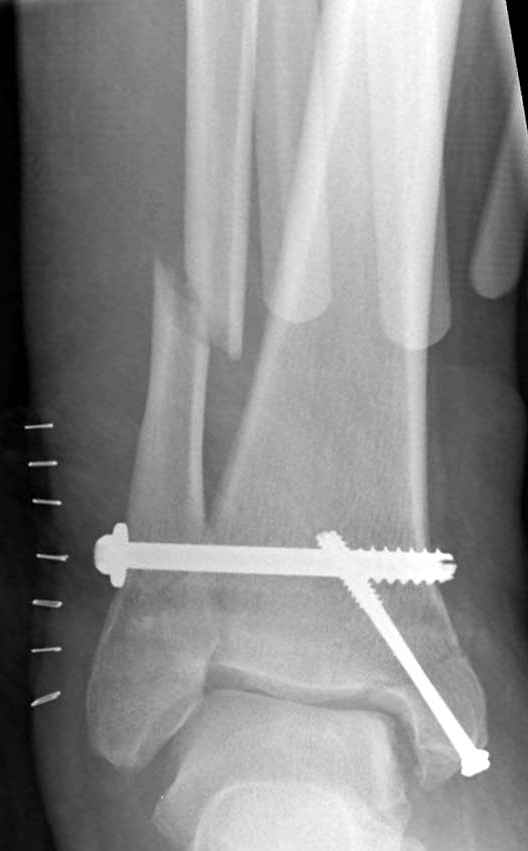

Ниже рентгенограммы

До операции 28 июля

Операция 29 июля

Через месяц

Боковой через месяц

15 ноября прямой

15 ноября боковой

15 ноября трехчетвертной

12 января прямой

12 января боковой

12 января трехчетвертной

Риторический вопрос - в каком руководстве рекомендован такой способ остеосинтеза наружной лодыжки?

Очевидно, такой результат операции был запрограммирован. При невосстановленной длине и практически нефиксированной малоберцовой кости (этот кортикальный винт - как карандаш в стакане), при неустраненном подвывихе, невправленной и тоже нефиксированной внутренней лодыжке нет стабильной вилки сустава. Если такую операцию сделать даже сразу, а не через 4 месяца, то результат ожидаем

тот же.

Вообще говоря, такое повреждение вполне успешно можно лечить без операции - если 6 недель подержать в гипсовом "сапожке" с хорошо устраненным подвывихом. Вероятное несращение внутренней лодыжки не обязательно компрометирует результат.

Ну а уж если выбран остеосинтез - нначать надо было с репозиции малоберцовой кости с точным восстановлением длины, с фиксацией треть-трубчатой пластиной по задней поверхности. Позиционный винт

избыточен - повреждение практически подсиндесмозное. А если бы

действительно было повреждение синдесмоза - в 4 месяца позиционный винт - не решение. Внутренню лодыжку такую - надо было бы спицами и проволочной петлей. Извините за эти банальности.

Вариант с артродезом уже обсудили. Хотя, после увиденых снимков, пессимизм насчет восстановительной операции у меня, например, несколько уменьшился. Особенного уж какого-то остеопороза не видно даже на январских снимках. Можно черед мини-доступы убрать винты, аппаратом вправить малоберцовую кость, устранить подвывих стопы. Ну а дальше фиксировать малоберцовую пластиной сзади. А может, и напряженной Y-спицей попробовать - Анатолий Федорович, как Вы полагаете? Внутреннюю - то, что осталось, если уже не получится сделать спицами и проволокой, то что-то типа пластики дельтовидной связки. А может, и не трогать ее вовсе... В общем, выбор непростой,

много факторов надо взвесить.

Если до сих ничего не сделано, с артродезом сустава в данный момент я бы повременил, на выставленных январских снимках хорошо сохранившийся сустав, а в "мортиз" (трехчетвертной) и на боковых снимках не менее 5 мм укорочение малоберцовой кости. Косые переломы лучше фиксировать пластинами, как то мы разбирали случай, где было отмечено, что это закон "таранная кость всегда следует за малоберцовой".

В данном случаи я бы уговорил больного на реконструкцию, для этого после удаления шурупов, спереди очистить от рубцов синдесмоз, несросшуюся наружную лодыжку - остеотомия по линии перелома и компрессирующий (lagging technique) кортикальный шуруп 3.5 мм по поперечнику остеотомии. Следующий этап - восстановление длины малоберцовой за счет удлинения, сделать поперечную остеотомию где-то на уровне сантиметр выше вашего синдесмозного шурупа, наложить длинную пластинку, прикрепить пластину за дистальный конец двумя или тремя шурупами; сохраняя контакт пластины с костью, имеющимся

compression&tension device AO system (при отсутствии любой lamina spreader подойдет, создать дистанцию между пластиной и шурупом, проведенным проксимальнее пластины) толкая проксимальный отдел пластины, низвести пластину, мортиз рентгенограмма подскажет на сколько. Если заранее сделать предоперационный план (ренгенограмма другой стороны), тогда точно можно определить, на сколько вам необходимо сделать поперечную остеотомию малоберцовой кости, для закрытия создавшегося дефекта.

Убедившись, что желаемая длина восстановлена, окончательная фиксация пластины, при этом через пластину пару 3.5 мм шурупов на синдесмоз, предпочтительно в четыре кортекса и оставить на 3 мм длиннее, если под нагрузкой синдесмотический шуруп сломается, сломанный конец легче удалить с медиальной стороны.